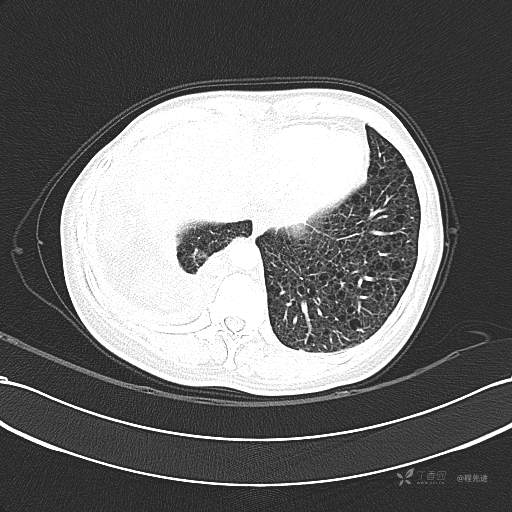

患者性别:女

患者年龄:51岁

简要病史:胸闷半年